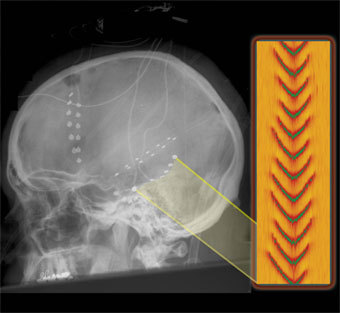

Энцефалограмма эпилептического припадка, изображение с сайта berkeley.edu

Сотрудники калифорнийского университета Беркли промоделировали электрический "шторм" в мозгу, сопровождающий эпилептические припадки. Статья, которая будет опубликована в Journal of the Royal Society в марте, должна способствовать развитию новых методов лечения эпилепсии, заявил один из авторов.

Было обнаружено, что, в отличие от нормальной мозговой деятельности, во время эпилептического припадка в коре головного мозга возникают когерентные бегущие электромагнитые волны. К решению медицинской проблемы исследователи привлекли стохастические дифференциальные уравнения в частных производных. Такие уравнения используются для описания биржевой активности, изменений климата и других явлений, находящихся под влиянием большой совокупности случайных факторов.

Пики на теоретической и экспериментальной энцефалограммах обладают одинаковой формой и близкими амплитудами, что подтверждает "работоспособность" метода. Расчеты, описывающие пока отдельные аспекты патофизиологии мозга, смогут в перспективе прояснить многие детали мыслительной деятельности, считает доктор Хейди Кирш (Heidi Kirsch), возглавляющий группу исследователей.